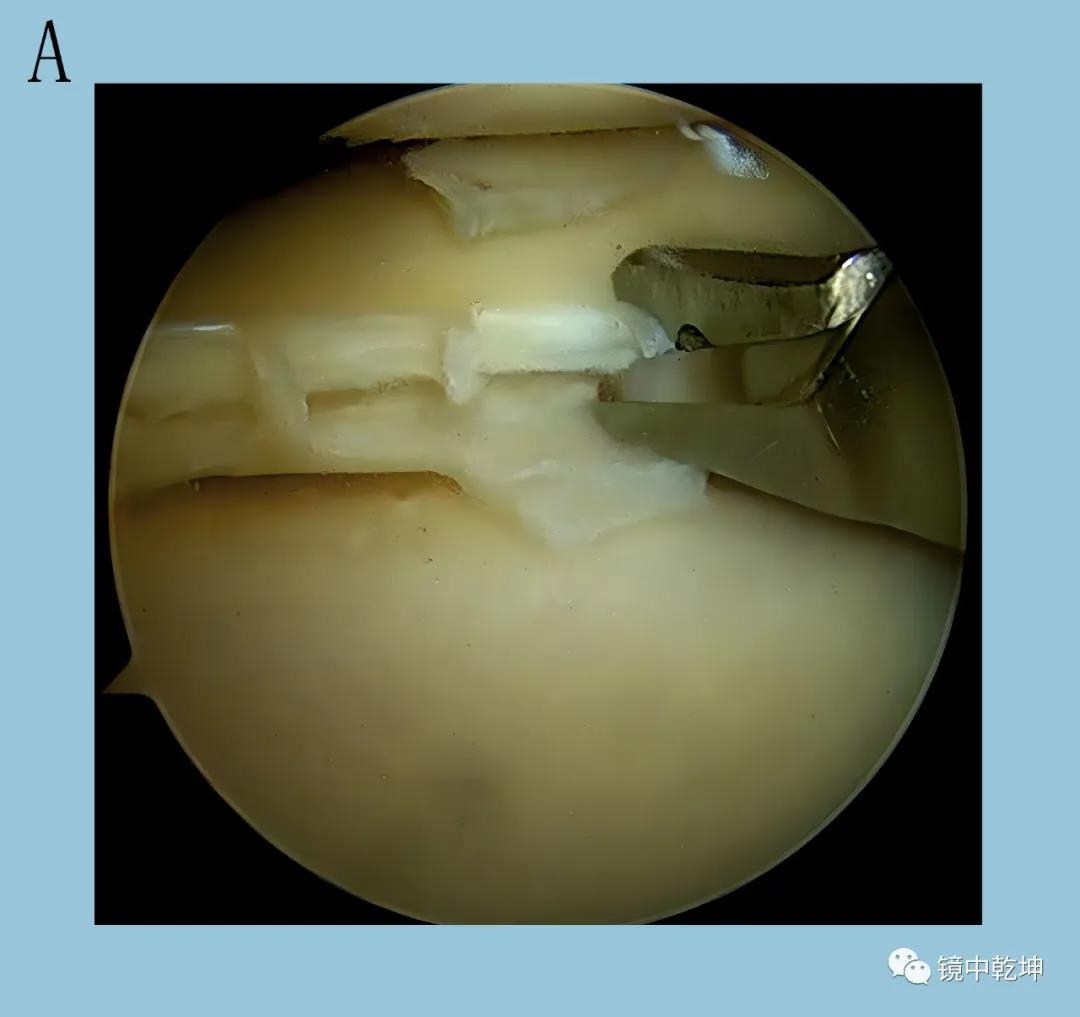

郝亮博士在关节镜下行手术治疗,手术仅用时13分钟,就解决了困扰陈女士的疼痛。术后陈女士膝关节处仅仅只有2个不到半厘米的小伤口,第二天就可以开始功能恢复锻炼了。

患者陈女士关节镜手术视野中

半月板层状撕裂全内缝合